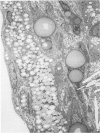

In rats with diet-induced hypercholesterolemia, two concomitant changes began to occur within 1 week and persisted for 1 year: an increase in total plasma cholesterol and an increase in the number of mononuclear cells adhering to the aortic intima (up to values 50 times normal). Adherent cells were approximately 90% monocytes and approximately 10% lymphocytes. Adhesion was focal, with some preference for ostia of aortic branches; it was followed by migration into the subendothelial space. The subendothelial monocytes/macrophages progressively became foam cells, thus giving rise to microscopic "fatty streaks." Ultimately, typical atherosclerotic plaques were formed. Four possible mechanisms of increased cell adhesion are suggested. Endothelial changes were mild; myelin figures arising from the endothelial surface were seen by electron microscopy. Endothelial denudation was never observed, neither in light-microscopic preparations stained with AgNO3 nor by ultrastructure. Platelet participation was minimal. It is concluded that in this model atherosclerotic plaques are initiated by mononuclear cell adhesion and emigration; endothelial denudation is not a necessary step in their pathogenesis.